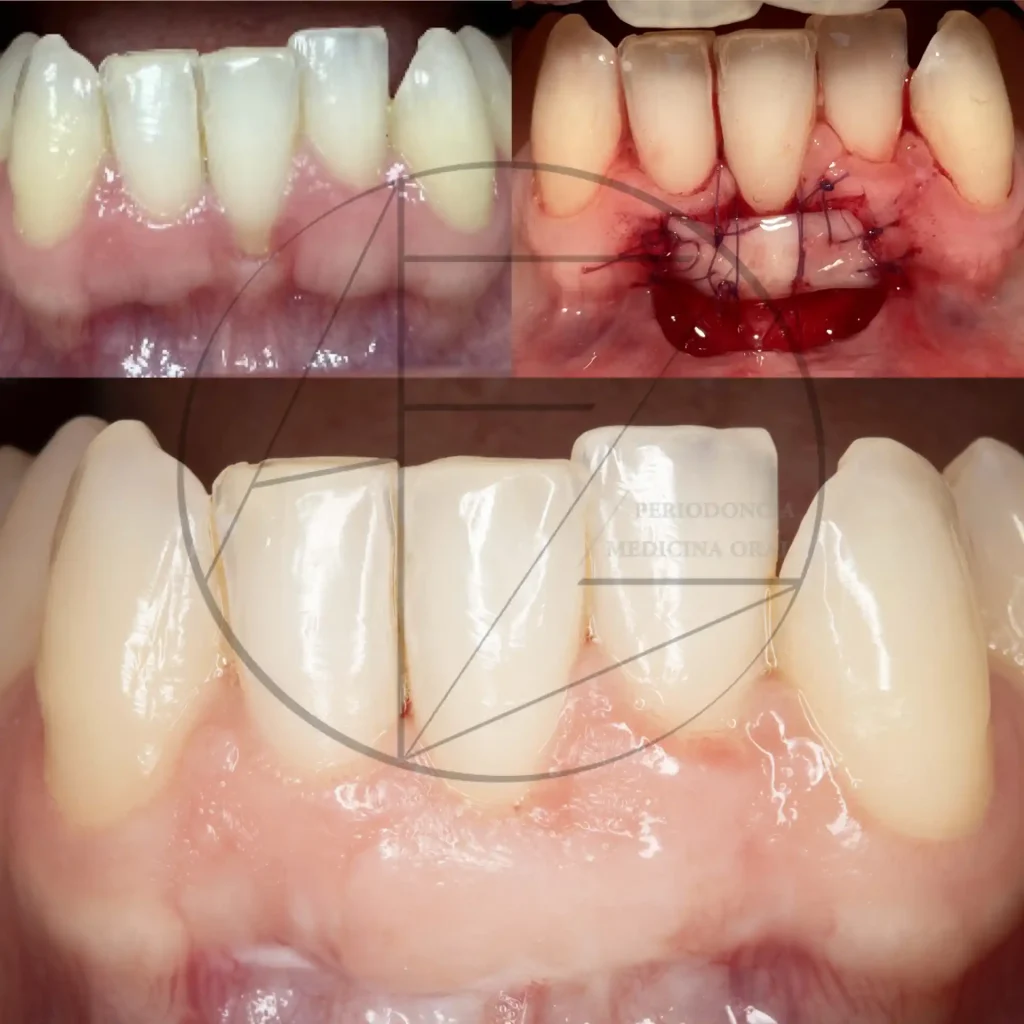

Casos clínicos

Fotos clínicas

Recesiones gingivales